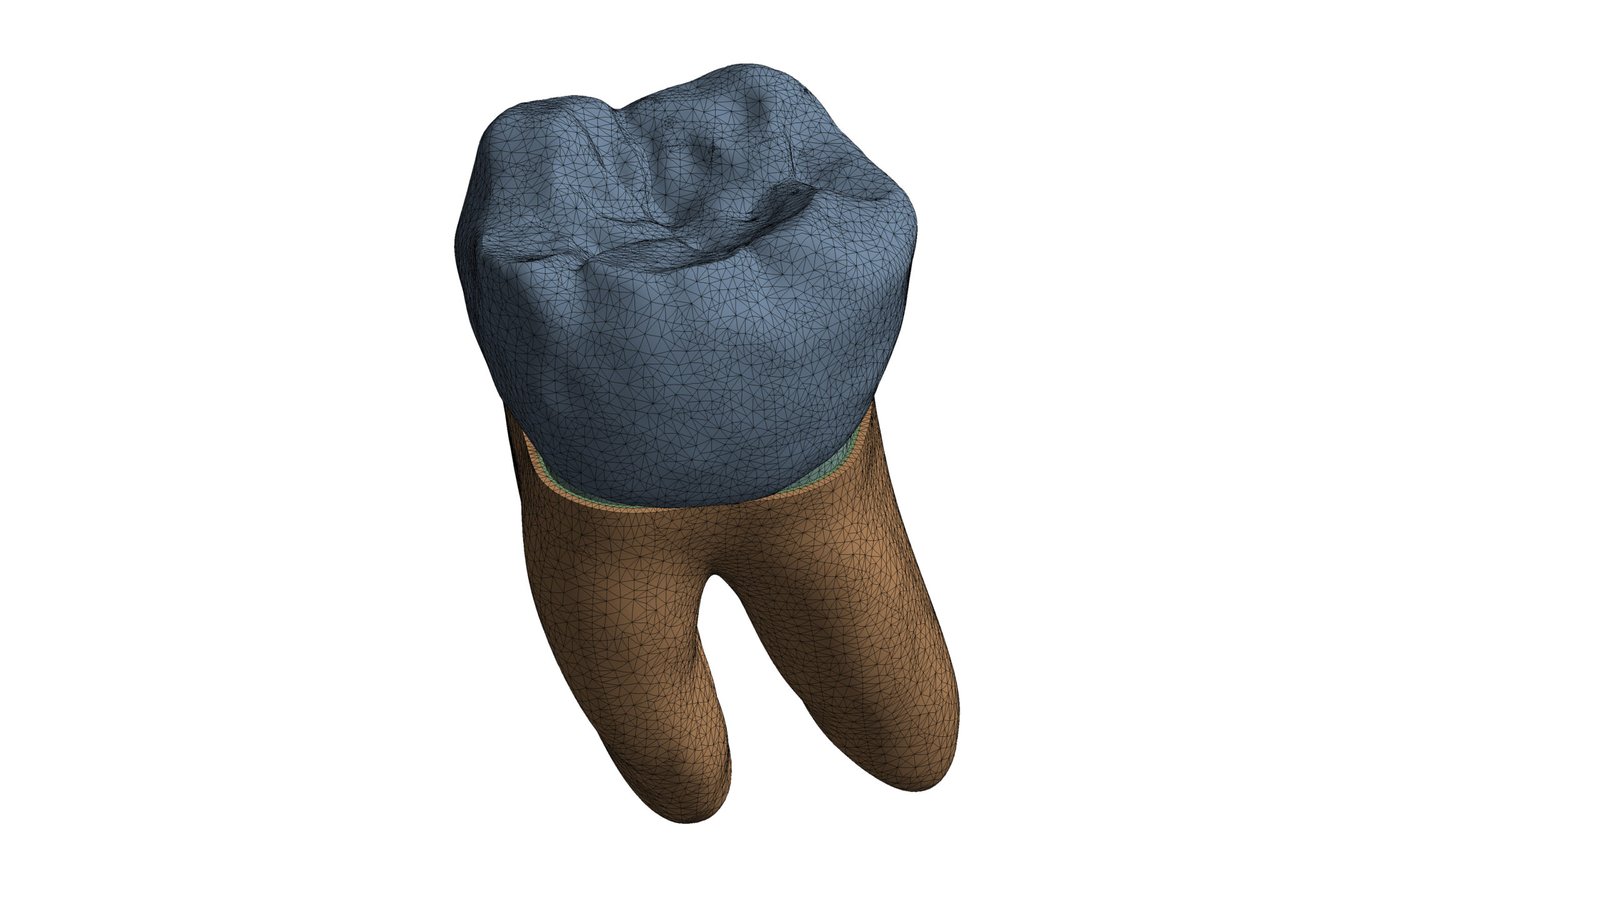

The Endodontic FEA section evaluates the biomechanical performance of root canal–treated teeth, endodontic tools, and reinforcement strategies. Through precise material characterization and micro-CT–based superimposition, we assess fracture risk, stress pathways, and instrument fatigue under various clinical scenarios. These simulations guide the selection of safer instrumentation techniques and restorative strategies. Our goal is to enhance predictability and reduce procedural complications.